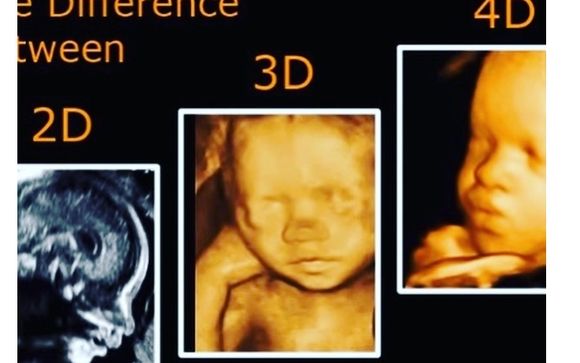

3d And 4d Imaging